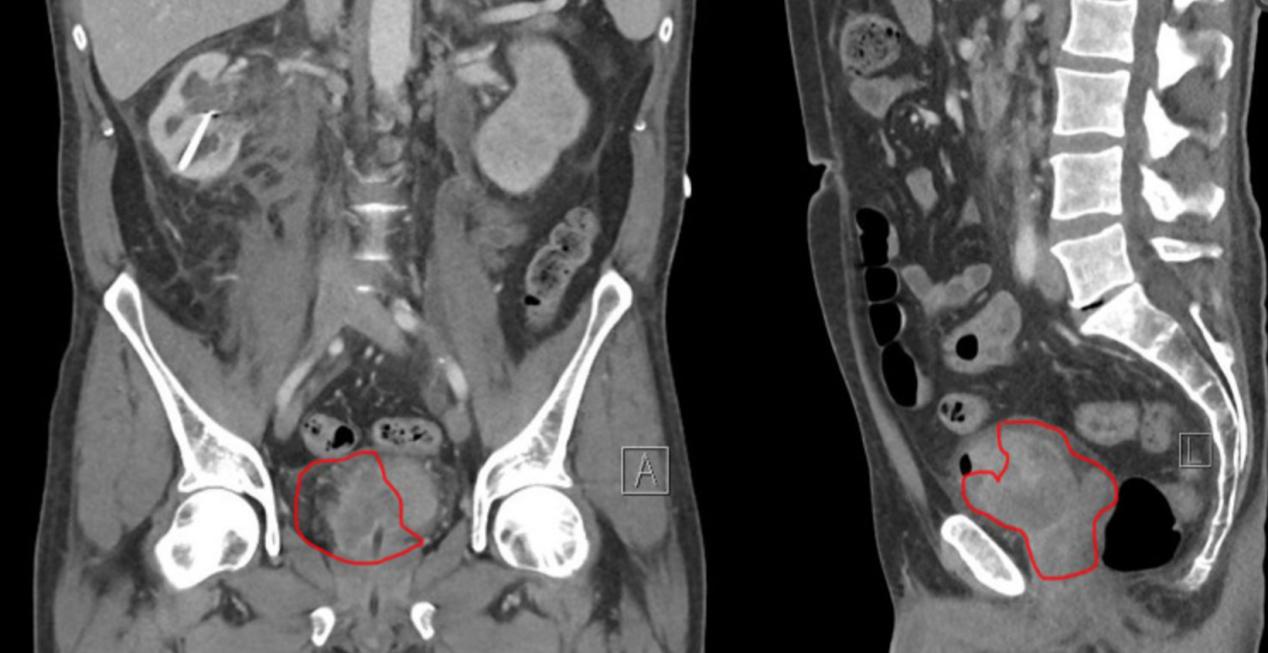

病人行双侧经皮肾造口术,定期进行血液透析,肌酐水平下降。入院后6天,行CT增强尿路造影和胸部增强CT检查,显示了一个巨大的右侧膀胱肿瘤,浸润了大约一半的膀胱和精囊(图1),主动脉旁淋巴结肿大。胸部未见转移。

图1 对比增强CT尿路造影,肿瘤的冠状(A)和矢状(L)视图(红线)。左侧(A)显示肿瘤延伸至膀胱。在右侧(L),肿瘤延伸到膀胱、前列腺和精囊